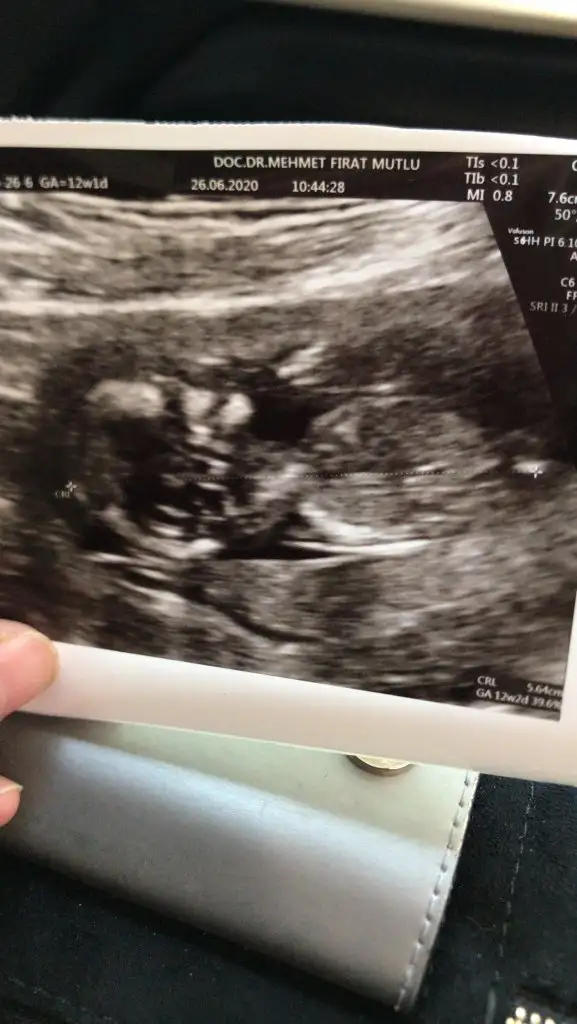

Kizlar yorumunuz

Eklentiler

• 70733DC5-F775-414D-9BD5-CCA598AFA0FF.webp

70733DC5-F775-414D-9BD5-CCA598AFA0FF.webp

10,8 KB · Görüntüleme: 44